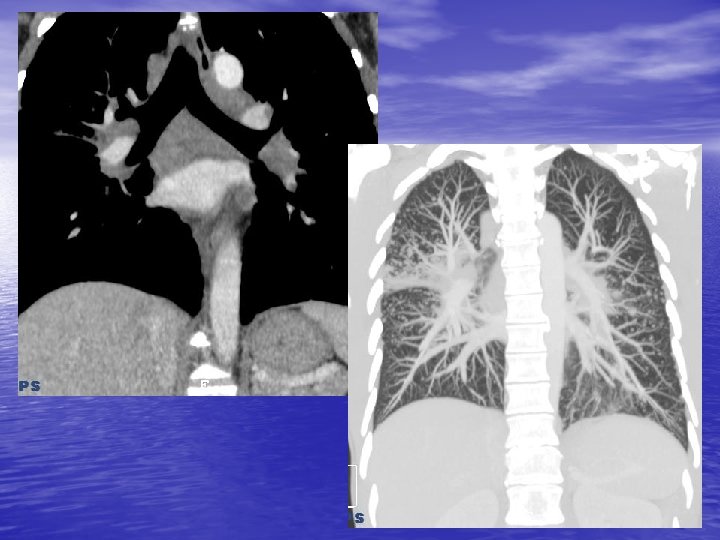

5. MASSE DU MEDIASTIN POSTERIEUR 5. 1. Tumeurs neurogènes - Tumeur des nerfs périphériques (schwannome, neurofibrome), des ganglions sympathiques (ganglioneurome, neuroblastome), paraganglionnaires (chémodectome). - ++ gouttières costo-vertébrales, parfois calcifications, lésions osseuses associées évocatrices (trou de conjugaison élargi). - Rôle ++ de l’I. R. M. pour le bilan (recherche de prolongement intra-rachidien).

5. 2. Autres tumeurs - Méningocèle. - Kyste neuroentérique. - Hématopoïèse extra-médullaire.